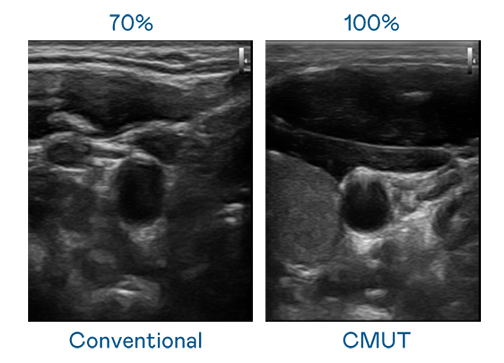

CMUT 技术是一种用电容式微机电元件来产生超音波讯号的技术。与传统 PZT 压电式技术相比,CMUT 频宽增加 30%,更宽频的超音波讯号让影像解析度大幅提升,是实现高影像品质医疗超音波扫描、促进精准医疗发展的关键技术。

超音波影像的解析度高低,首先取决于探头能发出的讯号频宽。MK体育官网 CMUT 可提供高清晰的超音波讯号,提供高频宽、高灵敏度、影像纹理细节更高的超音波影像,协助医护人员缩短影像判读时间及利用精准的医疗影像进行诊断。